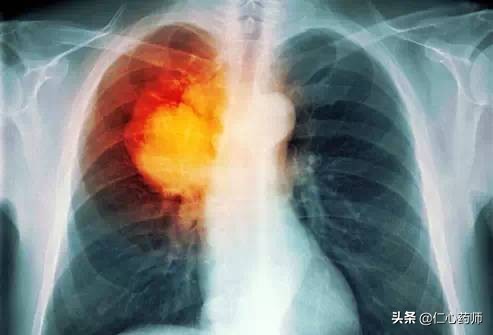

2.肺结节

肺结节在现在的健康体检中检出率比较高,肺结节是引起肺癌重要病变之一,可分为实性结节及磨玻璃结节。导致肺结节的原因比较多,如细菌性、结核性、霉菌性感染、错构瘤、肺硬化性血管瘤、血管滤泡性淋巴结增生、结缔组织病、尘肺以及肺恶性肿瘤等均可以形成肺部小结节,70% 有临床意义的肺小结节被证明是恶性肿瘤,无论是原发还是转移性的。

良性肺结节分为先天性和获得性两类 。 先天性肺结节有肺错构瘤 、支气管囊肿 、肺隔离症等 ;获得性肺结节又分为感染性和非感染性 ,包括机化性肺炎 、肺炎性肌纤维母细胞瘤 、炎性肉芽肿 、肺内淋巴结增生 、硬化性肺细胞瘤 、肺平滑肌瘤等 。手术切 除的良性肺结节中 ,最常见的是炎性肉芽肿, 其次是肺错构瘤 、肺内淋巴结增生 、肺平滑 瘤 、硬化性肺细胞瘤等。

因此出现肺结节要及时进行进一步检查。